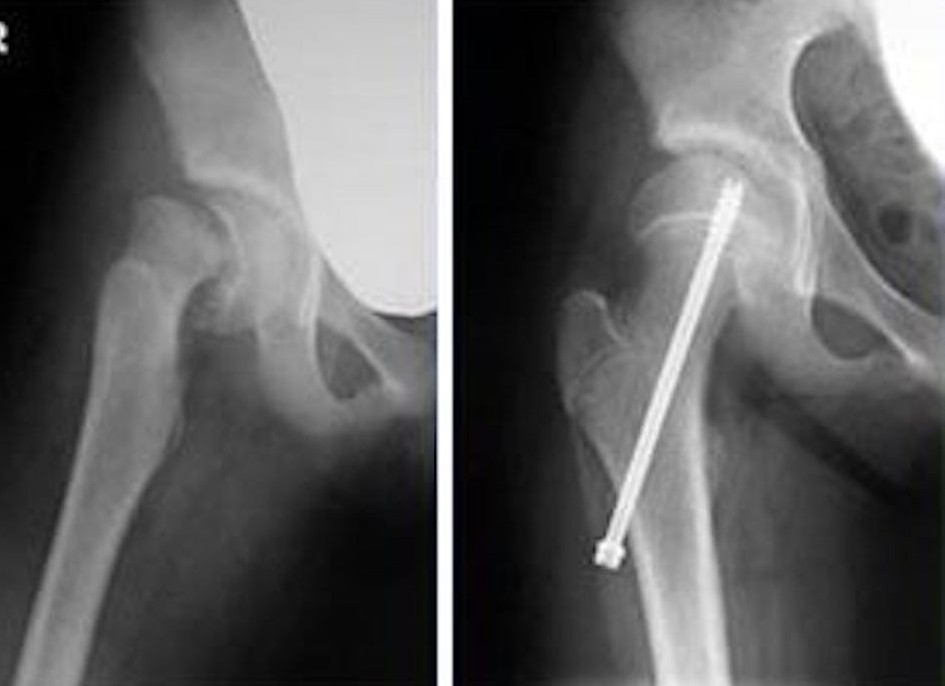

② 進行例では手術が必要なことも

骨が大きくずれている場合は、ピンやネジで骨を固定する手術が必要になります。

手術といっても比較的短期間で回復することが多く、

多くの子どもたちはその後、日常生活に戻ることができます。